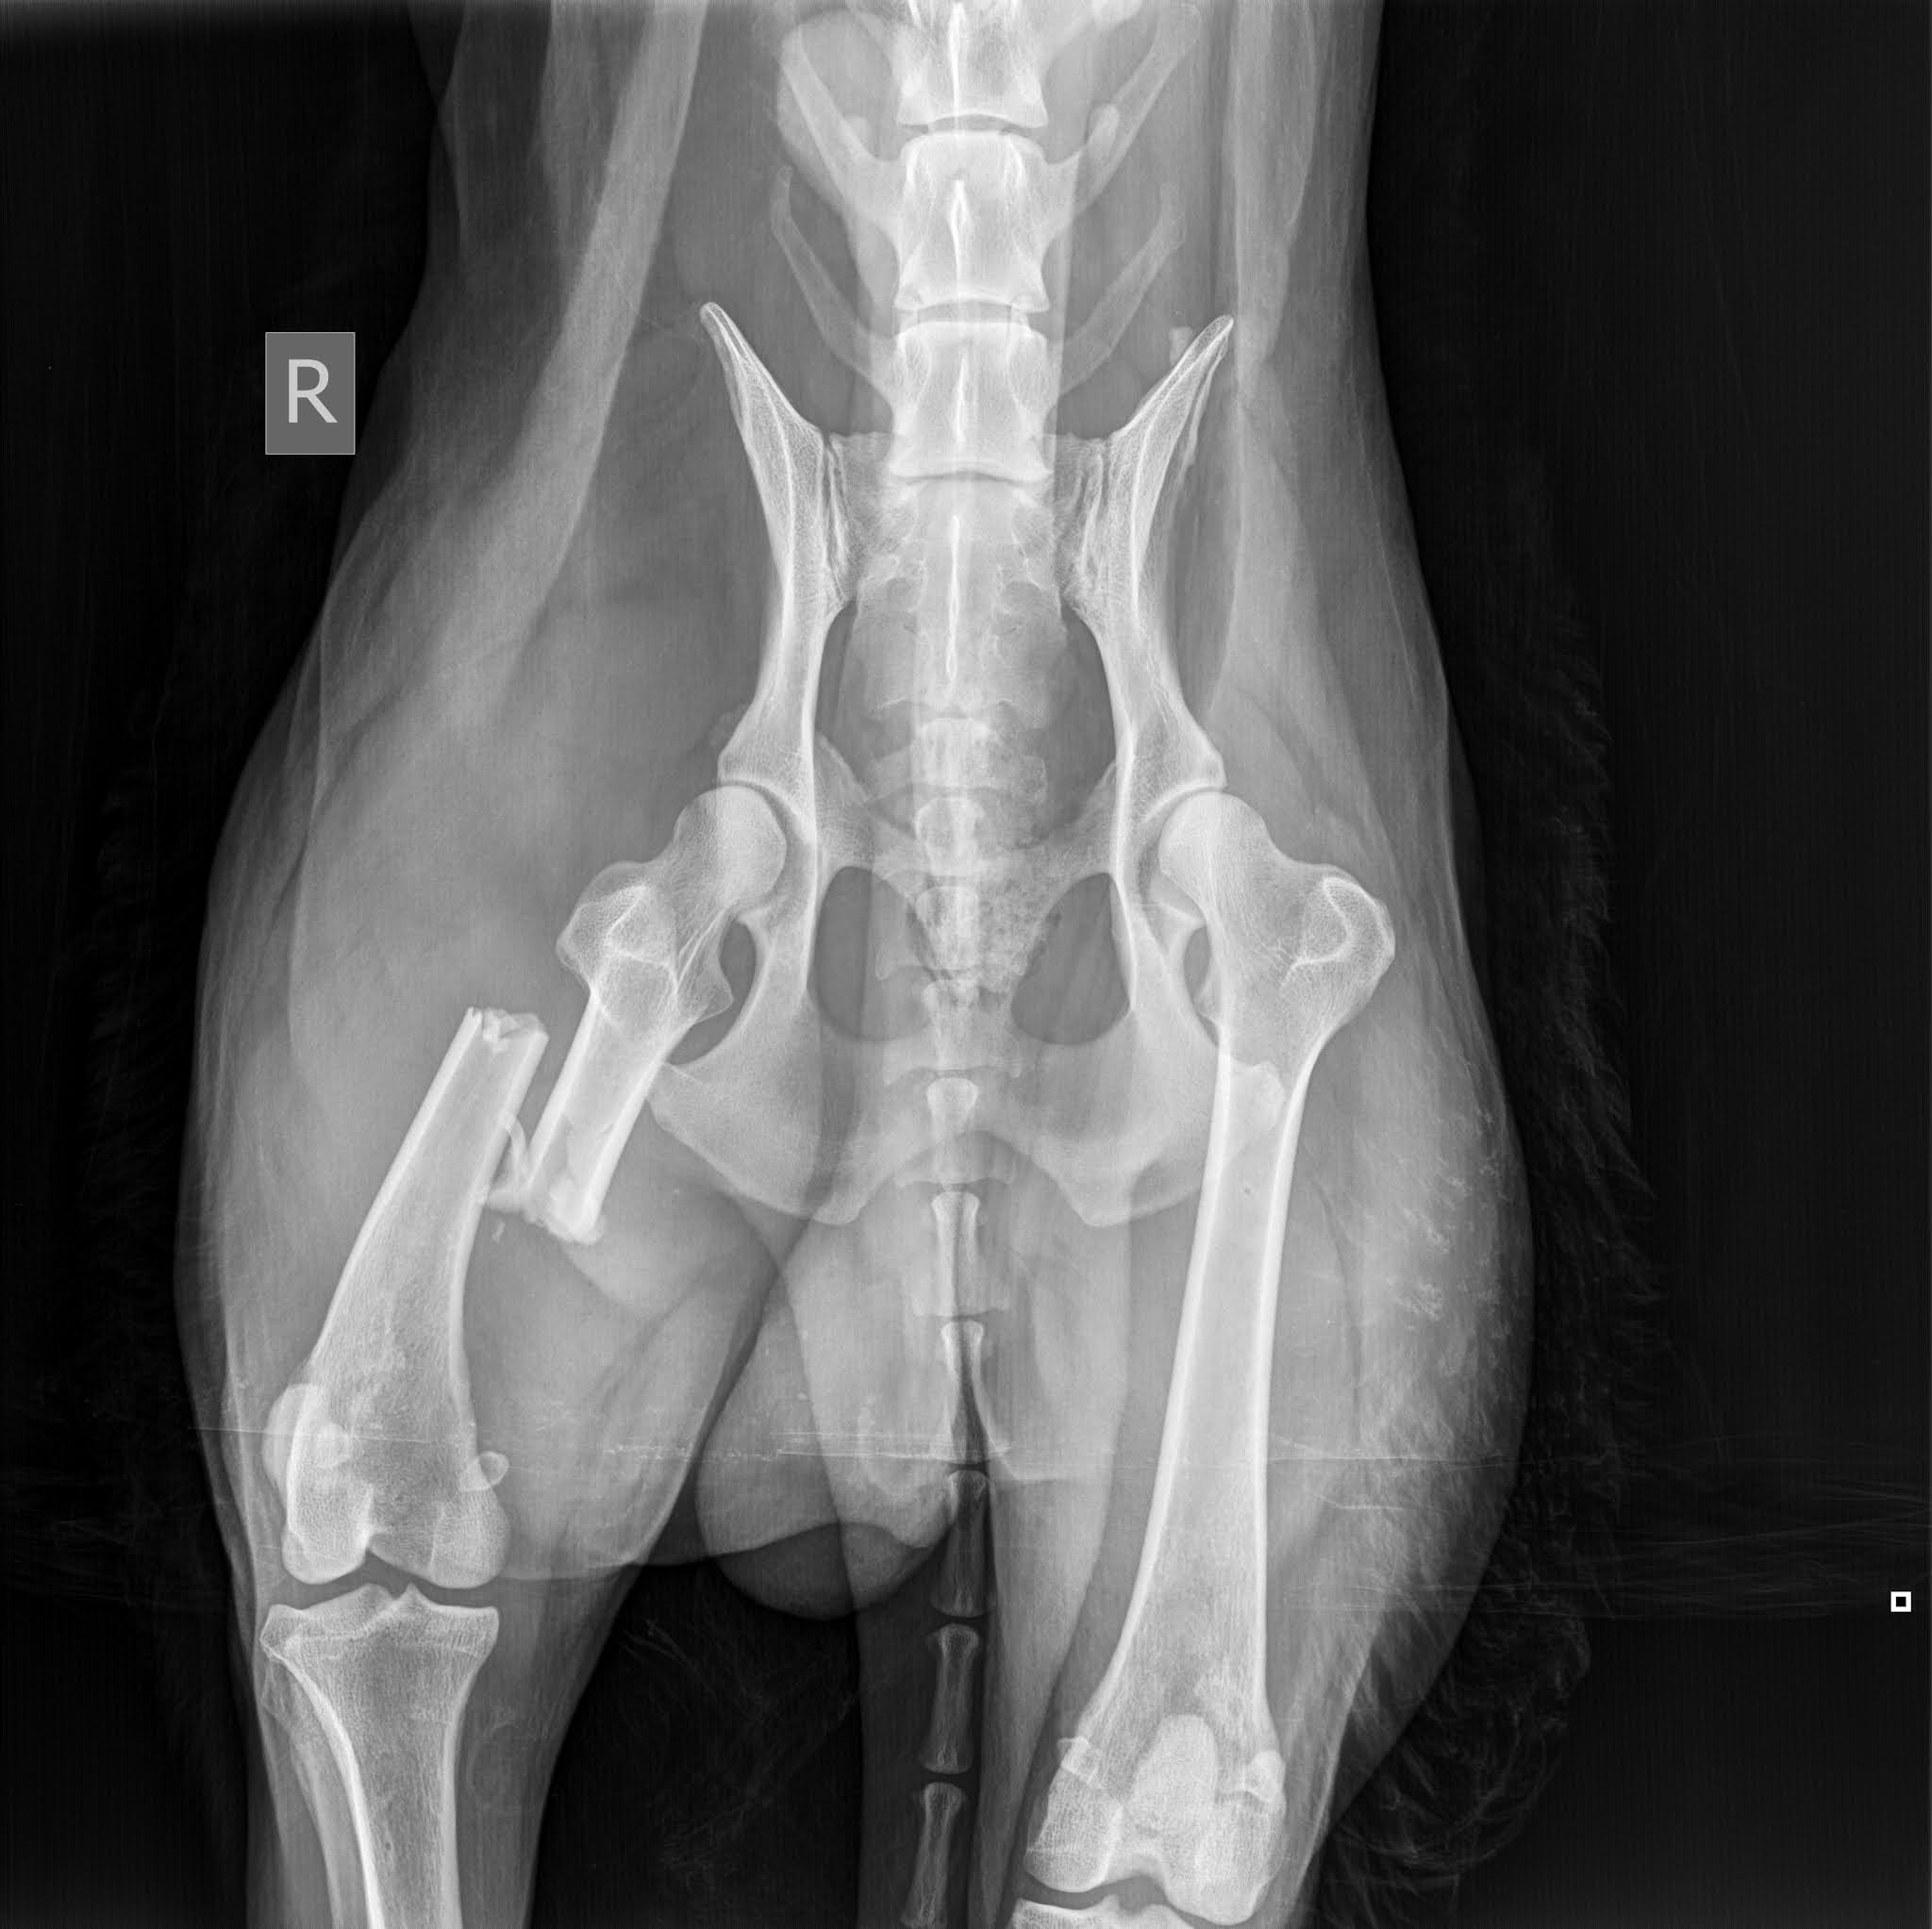

Signe põrutas ettenäidatud talusse ja seal valitsev olukord ning kõikjal vedelev koerasitt kinnitasid naabrinaise sõnu. Perenaist ennast polnud taas kodus. Ja tühja temaga ning edasi viis tee juba Tartusse Maaülikooli väikeloomakliinikusse. Uuriti-puuriti ja vaadati külmunud koerake üle. Röntgenpilt kinnitas traumat ja reieluu oli pooleks, mis pooleks. Õnneks mitte halva koha pealt ja seda annab lõdvalt lappida. Vaagen oli terve, siseorganid ka, aga täpsema selguse annab juba põhjalikum uuring.